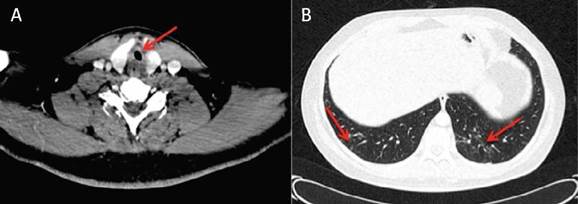

A las 72 horas reingresó por episodio de disnea con estridor. Se realizó tomografía axial computarizada (TAC), que mostró estenosis en el eje corto subglótico a 15 mm de la glotis, con una luz de 5 mm, sugerente de daño postintubación (Imagen 1a) y afectación pulmonar bibasal con fibrosis inferior al 10 % (Imagen 1b). Se realizó traqueostomía urgente. Se programó para dilatación traqueal con balón, guiado por fibrobroncoscopia, mediante el cual se obtuvo una luz adecuada y la posterior decanulación, sin incidencias.

Como pruebas complementarias se realizaron PCR (negativa) y serología (IgM e IgG positivas) para SARS-CoV-2. El TAC craneal y cervical no presentaron alteraciones, y la radiografía de tórax mostró un patrón compatible con neumonía COVID-19 evolucionada (Imagen 2b).